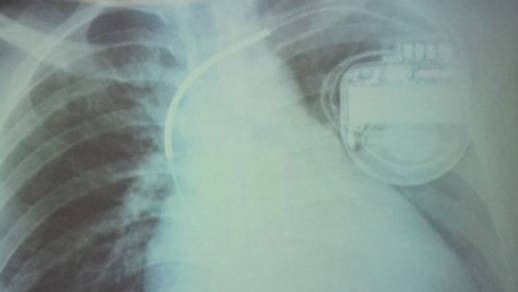

Hình ảnh cho thấy bệnh nhân đã được cài máy phá rung

Tại đây, qua kiểm tra, các bác sĩ phát hiện bệnh nhân bị yếu cơ tim thất phải gây loạn nhịp tim (250 lần). Bệnh này có thể dẫn đến ngất xỉu, đột tử bất cứ lúc nào. Các bác sĩ đã điều trị nội khoa kèm cấy vĩnh viễn vào người bệnh máy tạo nhịp tim để xung điện điều chỉnh nhịp tim, dự phòng những bất trắc sức khỏe có thể xảy đến.